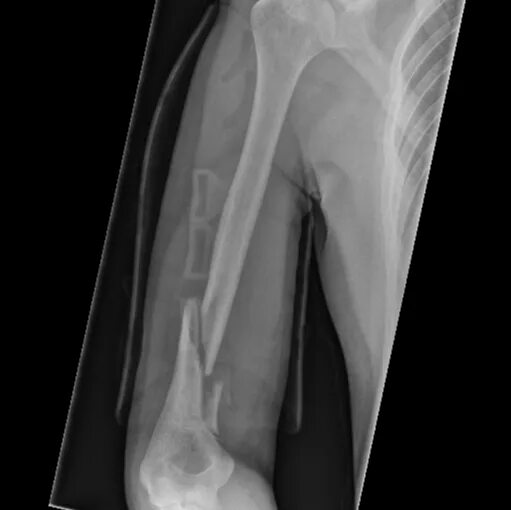

Оскольчатый перелом плеча со смещением